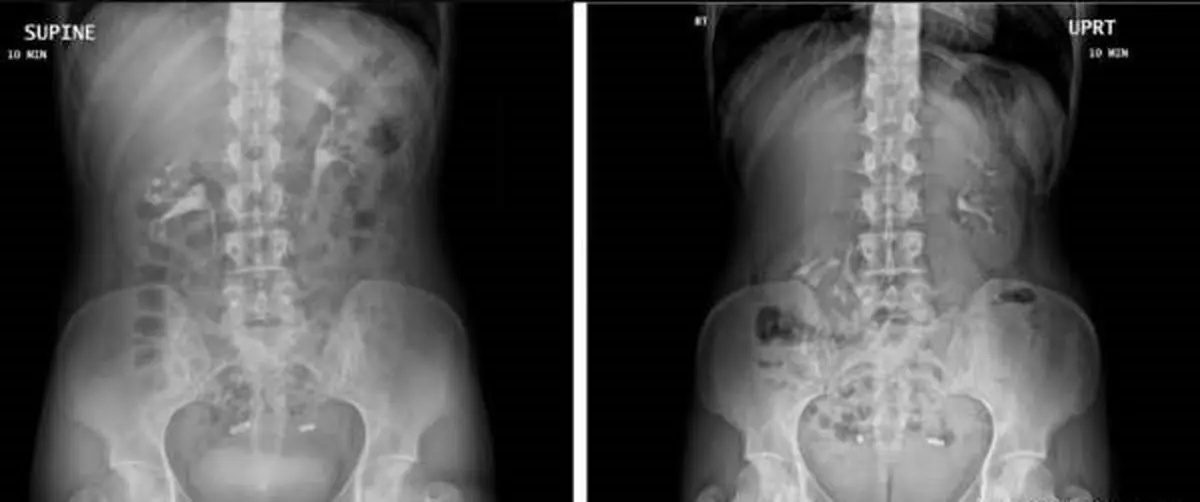

تشخیص کلیه متحرک و شناور با سی تی اسکن :

او می گوید :" کلیه شناور شرایط دشواری برای تشخیص دارد و بیماری شایعی نیست ، یکی از دلایلی که تشخیص این وضعیت را دشوار می کند این است ، سی تی اسکن در شرایطی انجام می شود، که فرد روی زمین دراز کشیده ، بنابراین به نطر می رسد کلیه ها در وضعیت عادی در بدن قرار دارند؛ پزشکان ممکن است مشکوک نشوند چیزی اشتباه است. او افزود زنان در این مورد، تنها زمانی درد را احساس می کنند که ایستاده باشند

هنگامی که اسکن در نهایت از کلیه زنان بطور ایستاده و دراز کشیده ،صورت گرفت تصاویر نشان دادند کلیه راست او هنگامی که ایستاده بود به سمت لگن حرکت کرده بود که این امر تشخیص کلیه متحرک را تایید کرد.